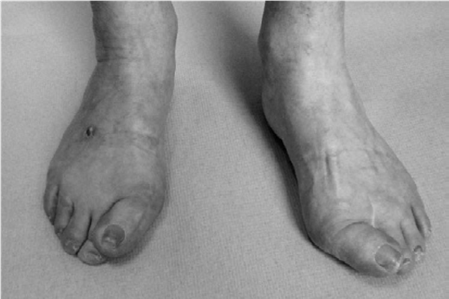

Foot and ankle structured oral questions6: Hallux valgus EXAMINER : Please have a look at these clinical phot…